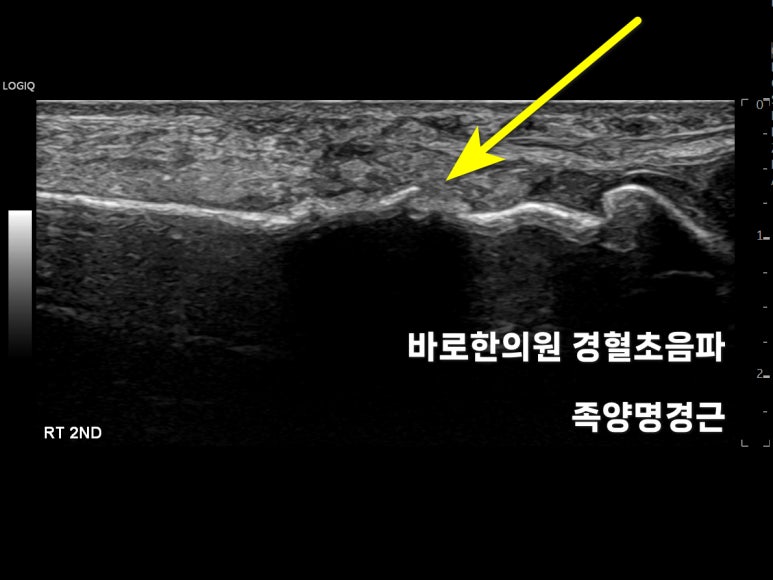

경혈초음파

족양명경근

먼저 다치지 않은 정상쪽,좌측 동일 부위의 영상입니다.

발등 중족골이

하얀 선으로

쭉 연결되어 있습니다.

이제 다친 쪽,오른쪽 2번째 중족골을초음파로 검사해봤습니다.

반대쪽처럼

뼈가 직선이 아니죠?

중족골이울퉁불퉁 지저분하게 보입니다.

최근 발등 골절로 생긴가골(callus) 입니다.

프로브를 돌려

엄지발가락과 비교해봅니다.

엄지 발가락은

곡선으로 깨끗한데,

두번째 발가락은

울퉁불퉁한 가골이 의심됩니다.